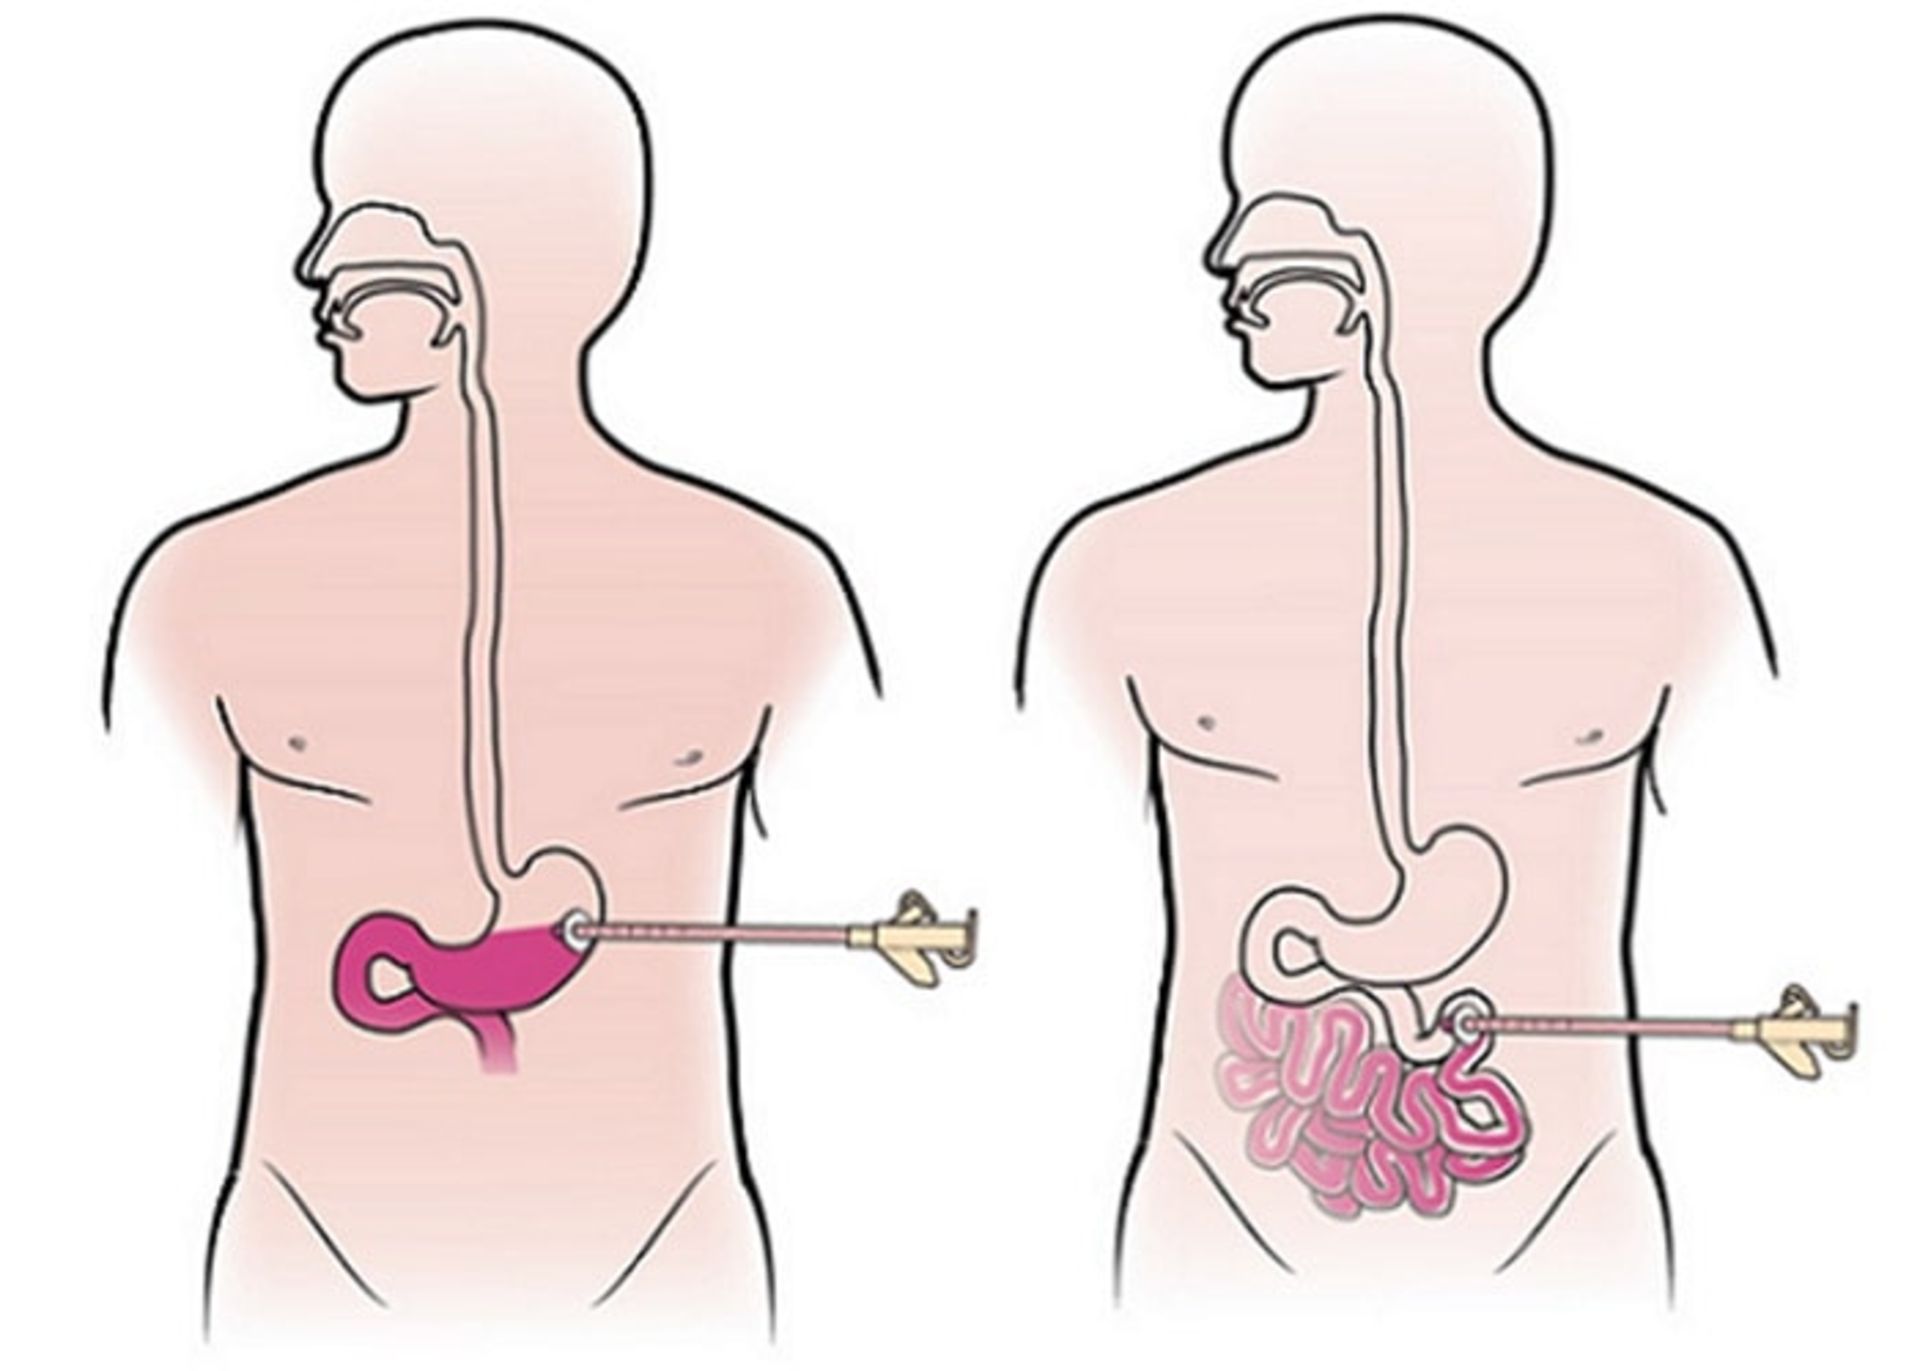

قرار دادن لوله غذا

برخی از افراد مبتلا به سرطان معده قادر نیستند بهاندازهی کافی غذا بخورند. در این وضعیت، یک عمل کوچک انجام میشود تا یک لولهی غذا ازطریق پوست ناحیهی شکم وارد قست دور معده یا رودهی کوچک شود. پس از آن مواد مغذی محلول میتواند مستقیما وارد لوله شود.